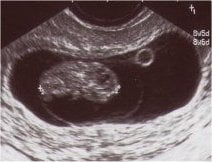

Baş popo mesafesi ölçümü normal değerleri